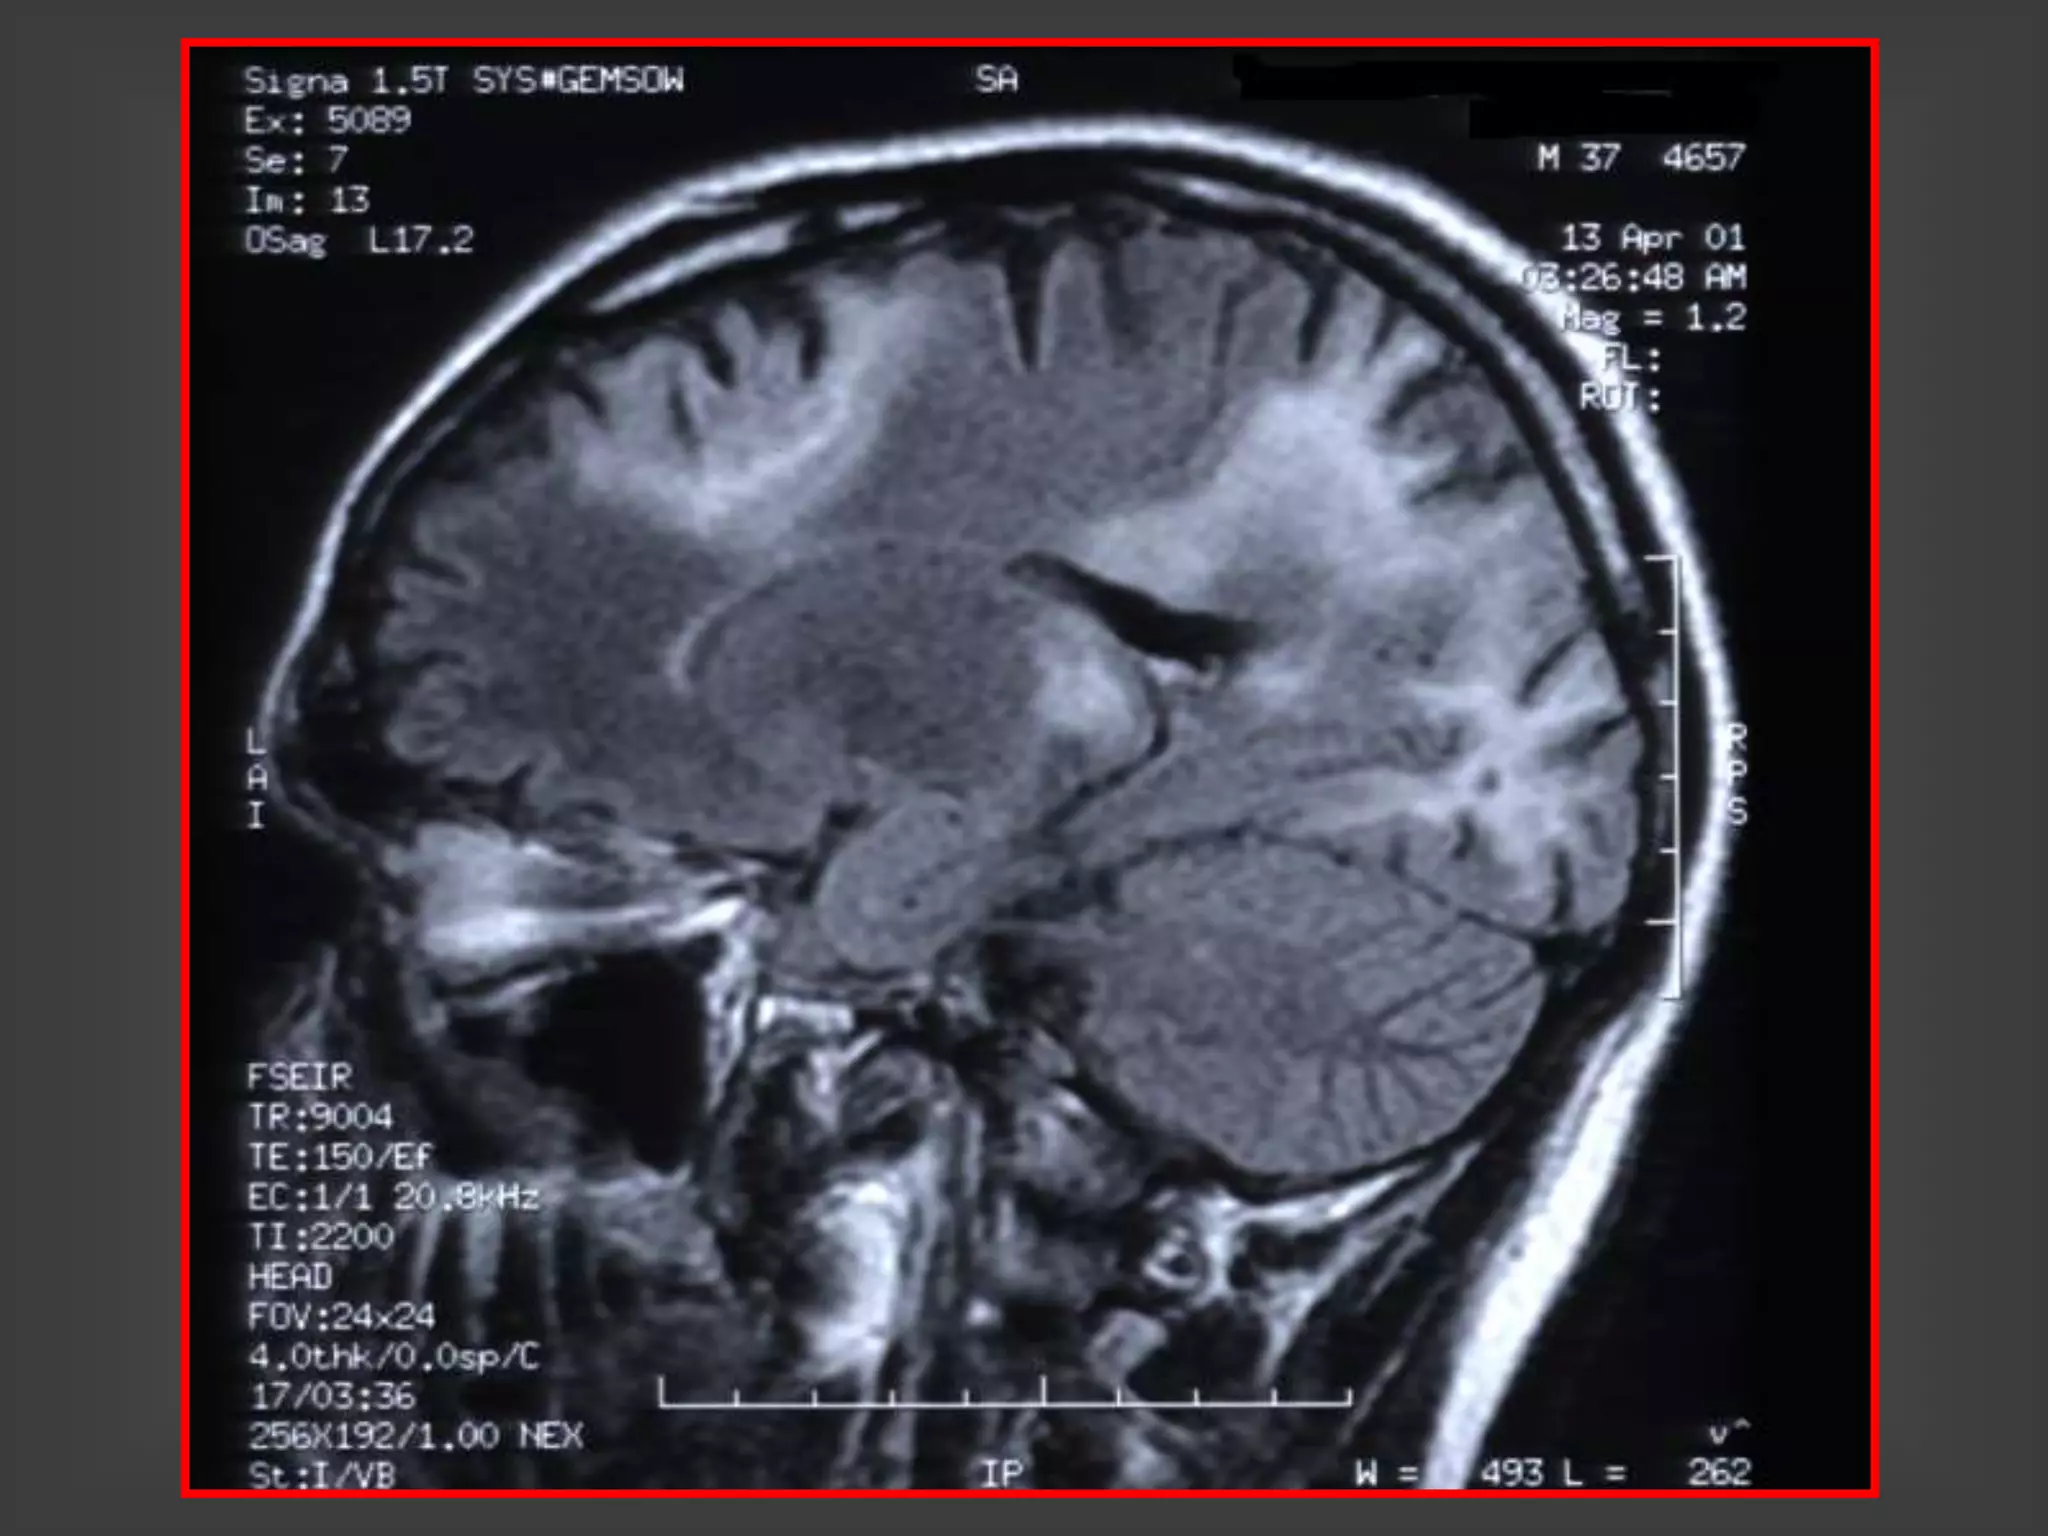

TOXOPLASMOSIS – RNM

LESIONES MÚLTIPLES

TOXOPLASMOSIS CEREBRAL-SIDA

HALLAZGOS EN LAS NEUROIMÁGENES

1. Lesiones hipodensas con refuerzo en anillo y edema

perilesional

2. Lesiones hipodensas sin captación del contraste con

edema perilesional

3. Lesiones nodulares (toman el contraste en forma

homogénea) y edema perilesional

4. Edema cerebral localizado sin lesiones focales visibles

5. TAC sin lesiones y RNM con lesiones focales

1 y 3: 80% a 90% de las lesiones